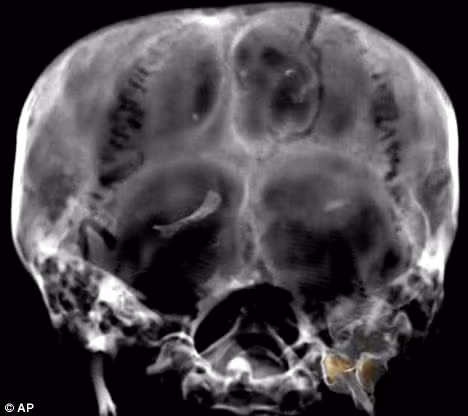

![]() |

| Hình ảnh hộp sọ vua Tut được quét cắt lớp chụp năm 2005 |

Các giả thuyết cho rằng ông bị ám sát vì là người cuối cùng cai trị triều đại và phía sau đầu của ông có một cái hố. Tuy nhiên, năm 2005, tiến sĩ Hawass tuyên bố rằng nhóm của ông đã không tìm thấy bằng chứng về cú đánh ở phía sau đầu và cái hố kia có từ quá trình ướp xác.